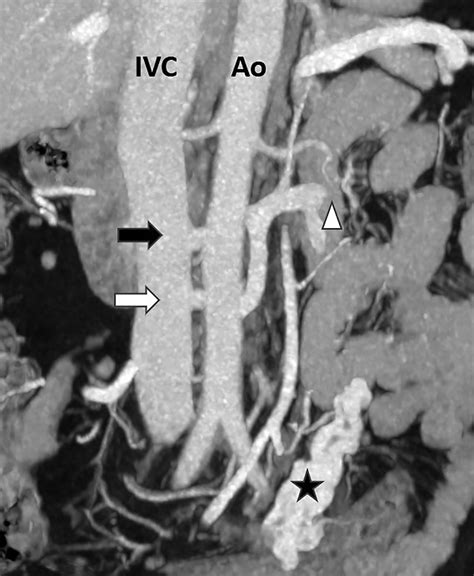

To grasp the mechanical nature of this condition, it is helpful to visualize the anatomy of the abdomen. The left renal vein travels horizontally across the abdomen to deliver blood from the left kidney into the inferior vena cava. In patients with Nutcracker Syndrome, the angle at which the superior mesenteric artery branches off the aorta is unusually narrow. This anatomical narrowing acts like a clamp, compressing the renal vein.

Diagnosing this condition requires advanced imaging techniques to visualize the vascular anatomy and confirm the compression. Doctors typically use a combination of non-invasive and invasive tests to determine the severity of the obstruction.

CT Angiography (CTA) Provides 3D images to measure the precise angle of the artery and the vein diameter.